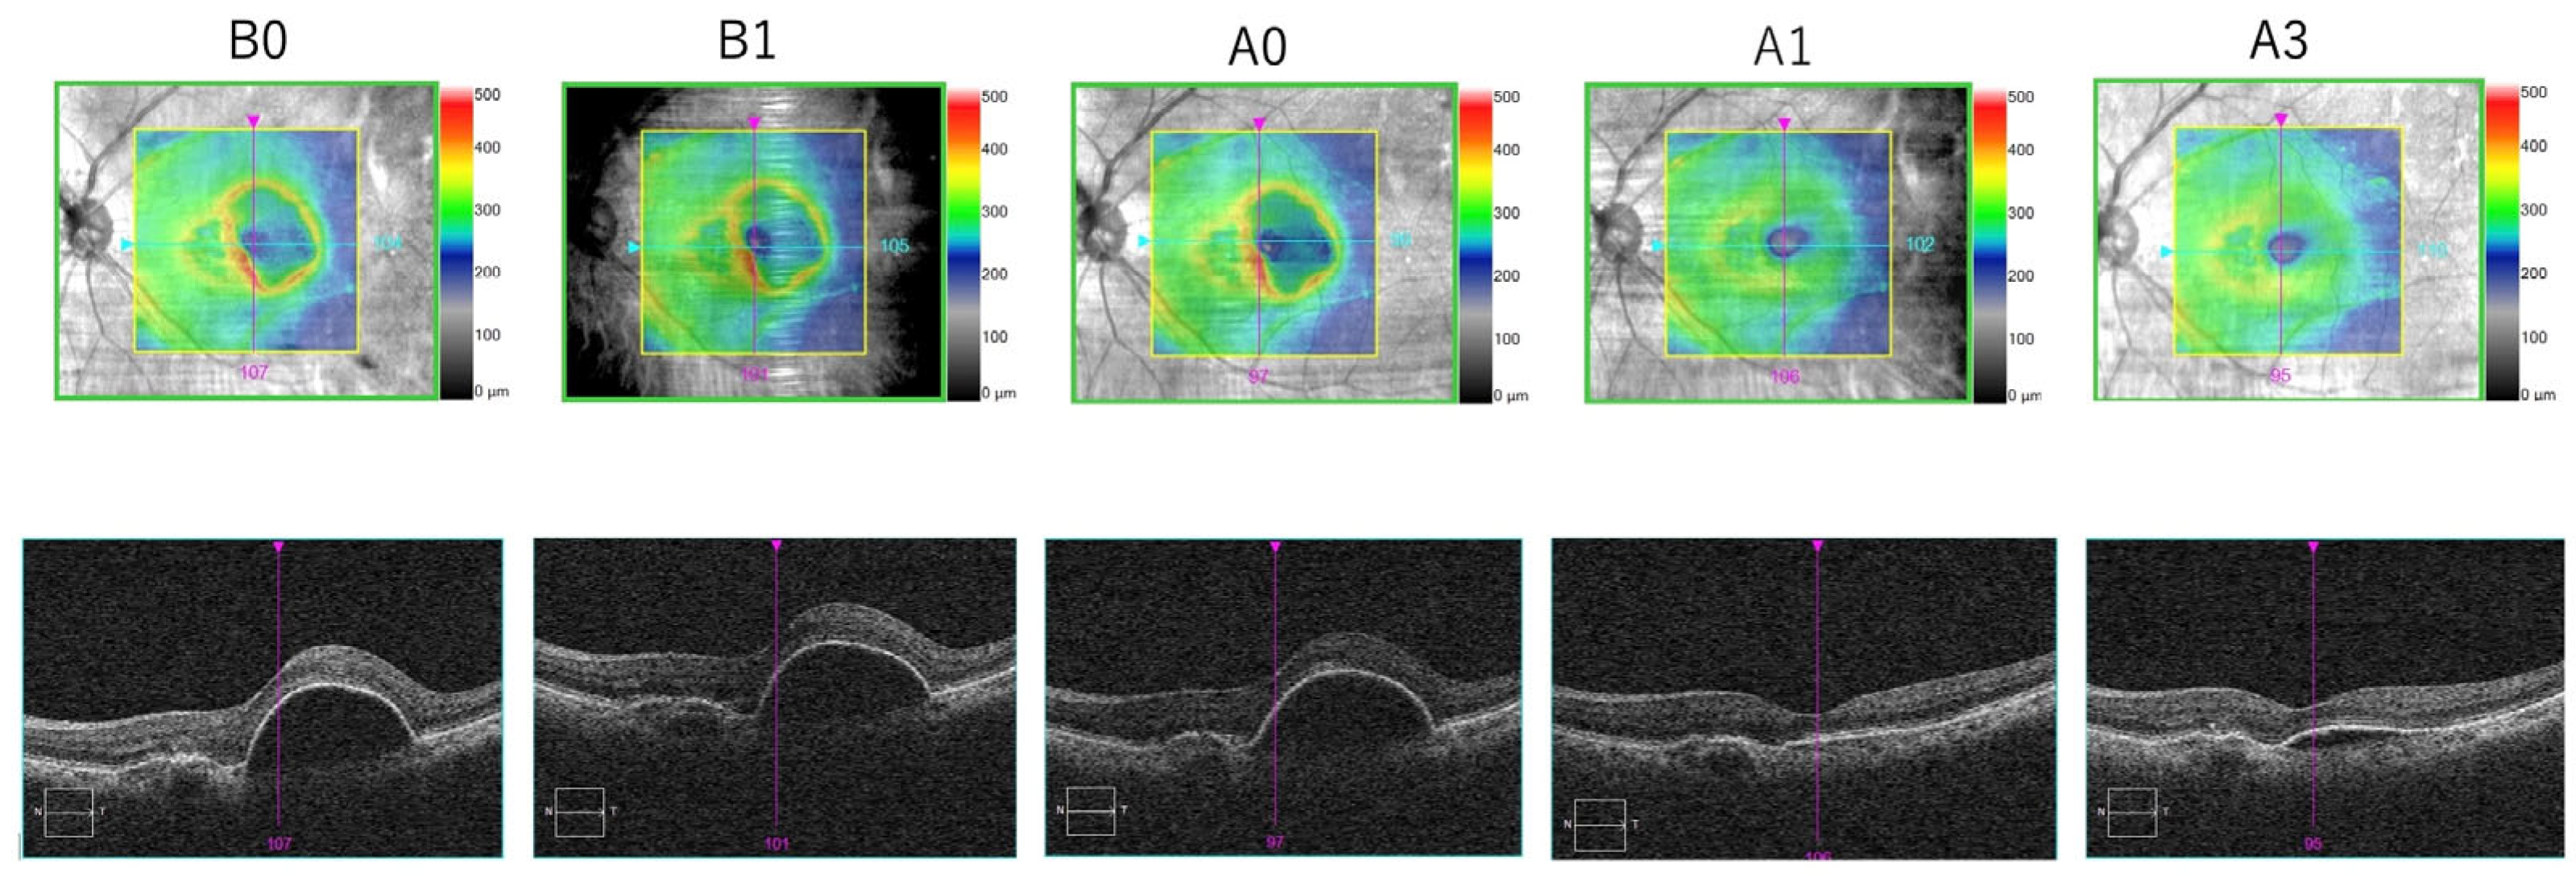

Figure 6 shows the follow-up of one of the patients included in our study.

Figure 6. A representative case of switching from IVA to IVBr in eyes with aflibercept-resistant nAMD. Optical coherence tomographic scans going through the fovea at B0, B1, A0, A1 and A3. After switching to brolucizumab, a decrease in CMT and the height of the pigment epithelial detachment was observed.